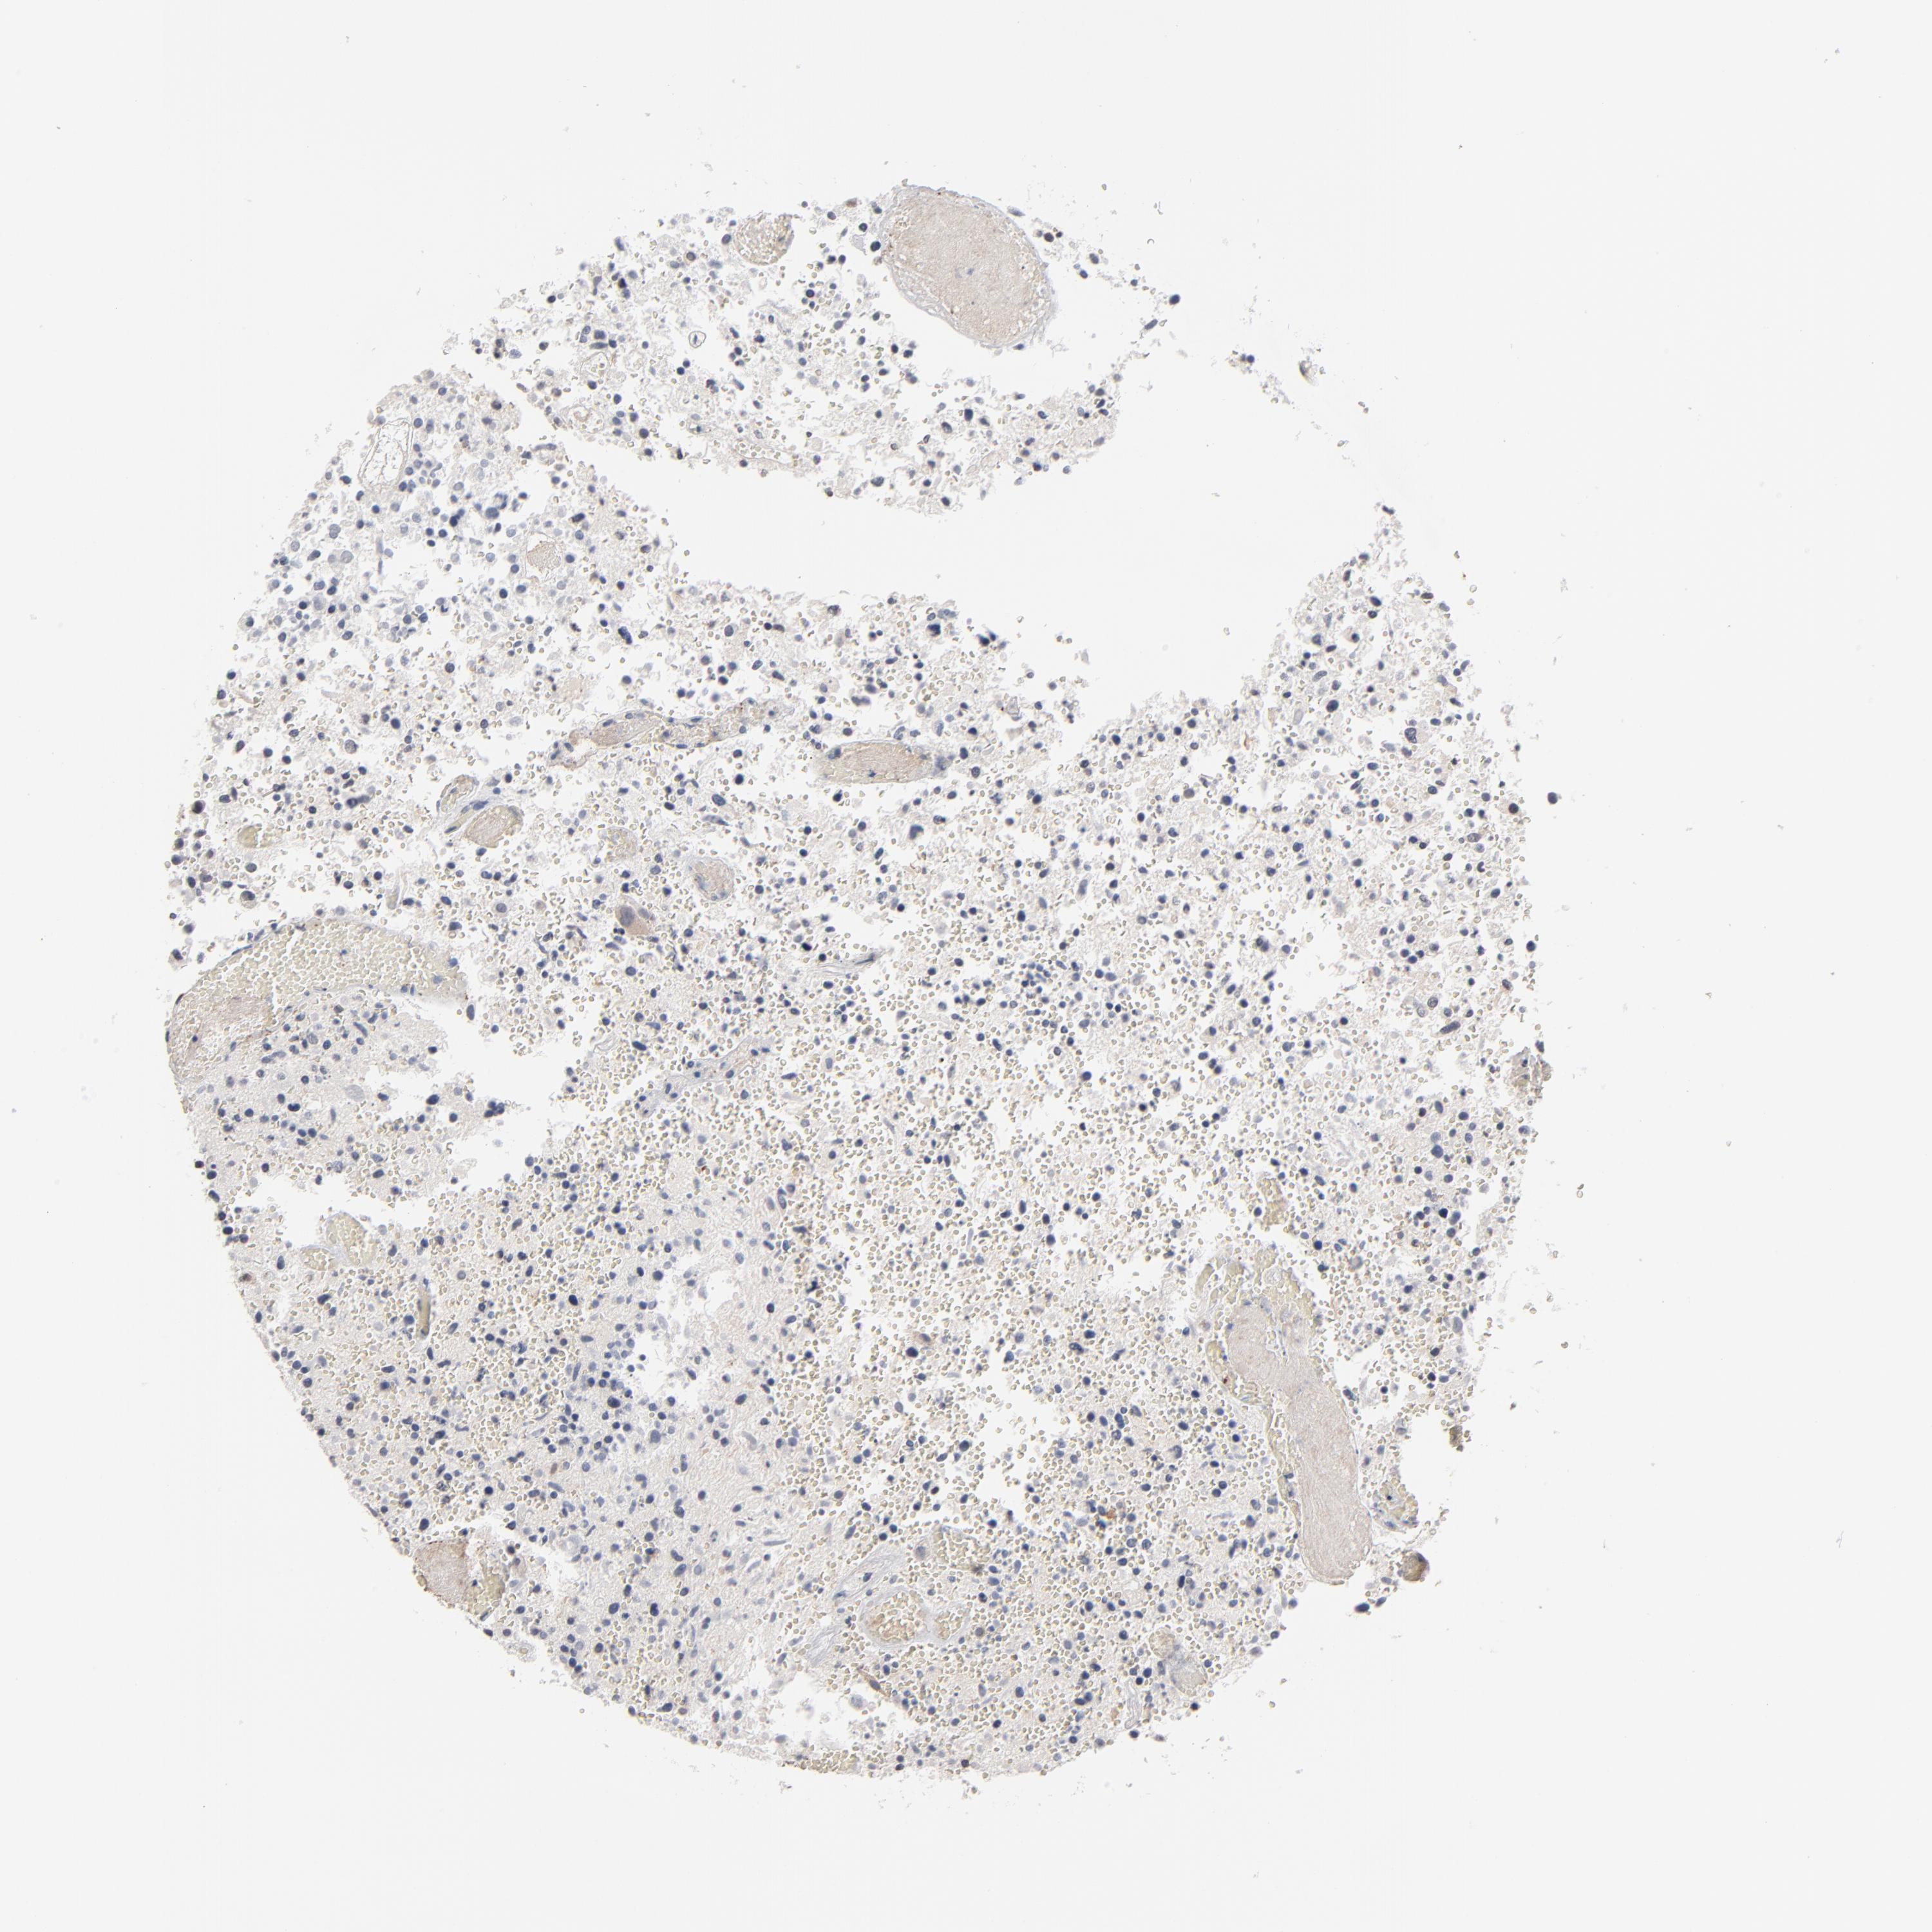

GLIOMA - Protein expressioni

A mouse-over function shows sample information and annotation data. Click on an image to view it in a full screen mode. Samples can be filtered based on level of antibody staining by selecting one or several of the following categories: high, medium, low and not detected. The assay and annotation is described here.

Note that samples used for immunohistochemistry by the Human Protein Atlas do not correspond to samples in the TCGA dataset.

Antibody stainingi

Antibody staining in the annotated cell types in the current human tissue is reported as not detected, low, medium, or high, based on conventional immunohistochemistry profiling in selected tissues. This score is based on the combination of the staining intensity and fraction of stained cells.

Each image is clickable and will lead to virtual microscopy that enables deeper exploration of all samples and also displays staining intensity scores, fraction scores and subcellular localization as well as patient and tissue information for each sample.

Antibody HPA001860

Antibody CAB013108

Staining

High

Medium

Low

Not detected

Intensity

Strong

Moderate

Weak

Negative

Quantity

>75%

75%-25%

<25%

None

Location

Nuclear

Cytoplasmic/membranous

Cytoplasmic/membranous,nuclear

Glioma, malignant, High grade

Glioma, malignant, Low grade